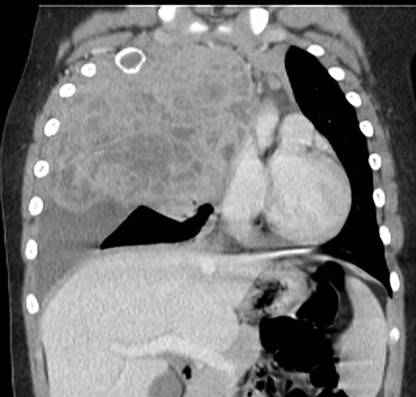

Dada la clínica se decide realizar radiografía de tórax (Figura 1) en la que se identifica derrame pleural derecho y una masa en segmento anterior del lóbulo superior derecho (LSD) con una lesión lítica expansiva en el segundo arco costal anterior derecho. Se amplia estudio con ecografía en la que se visualiza una masa pleural / pulmonar en segmento anterior de LSD con probable afectación mediastínica, derrame pleural derecho y alteración en la cortical del segundo arco costal anterior derecho. Se decide realizar TC torácico con contraste (Figura 2), (Figura 3) y (Figura 4) para valorar extensión y características de la lesión, identificándose una masa de aproximadamente 120x130x100 mm que ocupa casi todo el hemitórax derecho, heterogénea, con múltiples áreas quístico-necróticas en su interior. Condiciona desviación contralateral del mediastino y su infiltración, comprimiendo la vena cava inferior, sin claro plano de separación y contactando con el pericardio con signos de infiltración de la aurícula derecha. Comprime el bronquio principal derecho y sus ramas, condicionando atelectasia parcial secundaria y contacta con el segmento extrapericárdico de la arteria pulmonar derecha y ambas venas pulmonares derechas.

Figura 2: Masa de aproximadamente 120 x130 x 100 mm que ocupa casi todo el hemitórax derecho, heterogénea con múltiples áreas quístico-necróticas en su interior. Desviación contralateral del mediastino e infiltración del mismo, comprimiendo la vena cava inferior, sin claro plano de separación y contactando con el pericardio con signos de infiltración de aurícula derecha. Comprime el bronquio principal derecho y sus ramas, condicionando atelectasia parcial secundaria y contacta con el segmento extrapericárdico de la arteria pulmonar derecha y ambas venas pulmonares derechas.